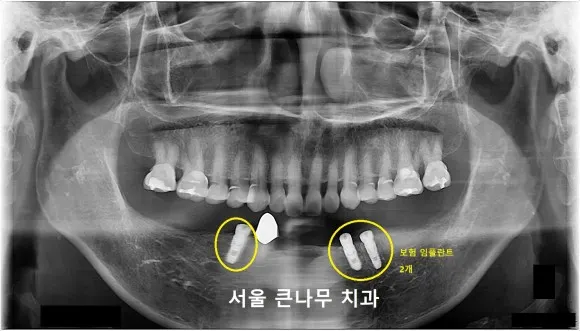

65세 이상은 보험 임플란트 2개가 적용되기에 임플란트 총 3개를 식립하였지만 2개의 보험 적용으로 경제적인 부담을 많이 줄일 수 있었습니다.

임플란트 식립 후 기다리는 두 달여의 기간 동안 아래턱에 하나 남은 이는 심미성과 기능성을 위해 PFM 크라운으로 교체해 주었습니다. 또한, 두 달여간의 기간 동안 틈틈이 보험 적용이 되는 부분틀니 제작에 들어갔기 때문에, 임플란트 크라운을 씌어주는 기간에 맞춰 오래 기다리지 않고 틀니 제작을 완성할 수 있었습니다.